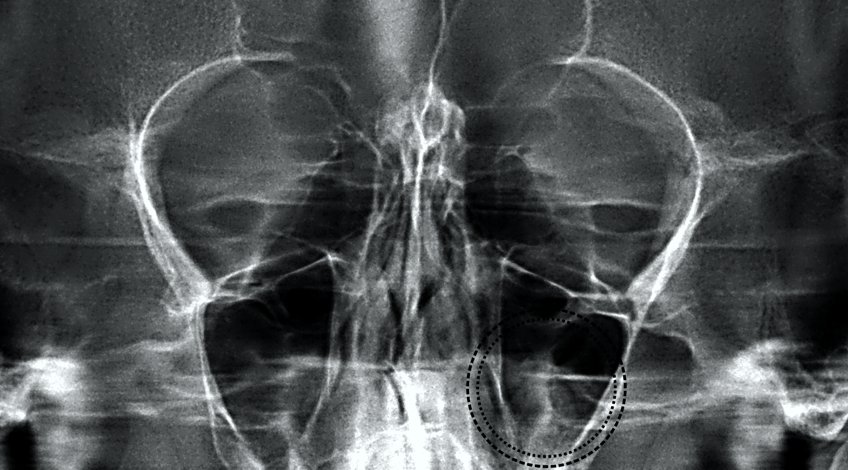

Radiografías, Imagenes de Cavidades Perinasales

Una radiografía de senos paranasales corresponde a un estudio imagenológico que utiliza rayos X para observar sus senos paranasales. Los senos paranasales son bolsas (cavidades) llenas de aire cerca del conducto nasal. Existen cuatro pares de cavidades que se conectan con la cavidad nasal a través de pequeños orificios o canales.(frontales, maxilares, etmoidales y esfenoidales)

Tu médico tratante la puede pedir para estudio de cefalea (dolor de cabeza), estudio de síndrome febril, lesión en los senos paranasales, sospecha de inflamación (sinusitis), tumores u otras masas, etc. Esta radiografía es simple y rápida y no involucra que se coloque ningún instrumento en su cuerpo (no es invasiva)